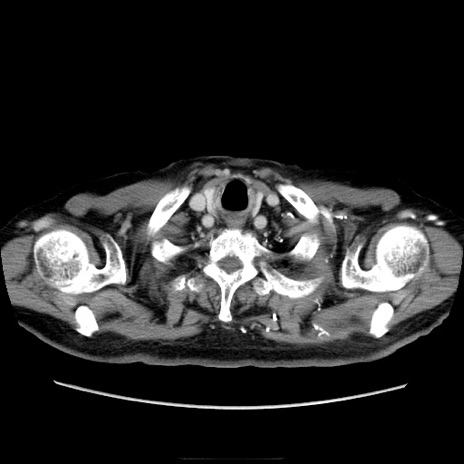

冠状断像

【症例】70歳代男性

【主訴】腹痛

【現病歴】肝硬変・肝細胞癌にてかかりつけの方。約9時間前に食後より腹痛出現。症状が徐々に増悪し、嘔吐出現したため来院。

【既往歴】肝硬変、肝細胞癌(RFA、TACE後)

【身体所見】意識清明、表情苦悶様、BT 36℃、BP 129/78mmHg、P 88bpm、SpO2 97%(RA)、右上腹部から心窩部にかけて圧痛あり、反跳痛なし、筋性防御あり。

【データ】WBC 5800、CRP 0.16